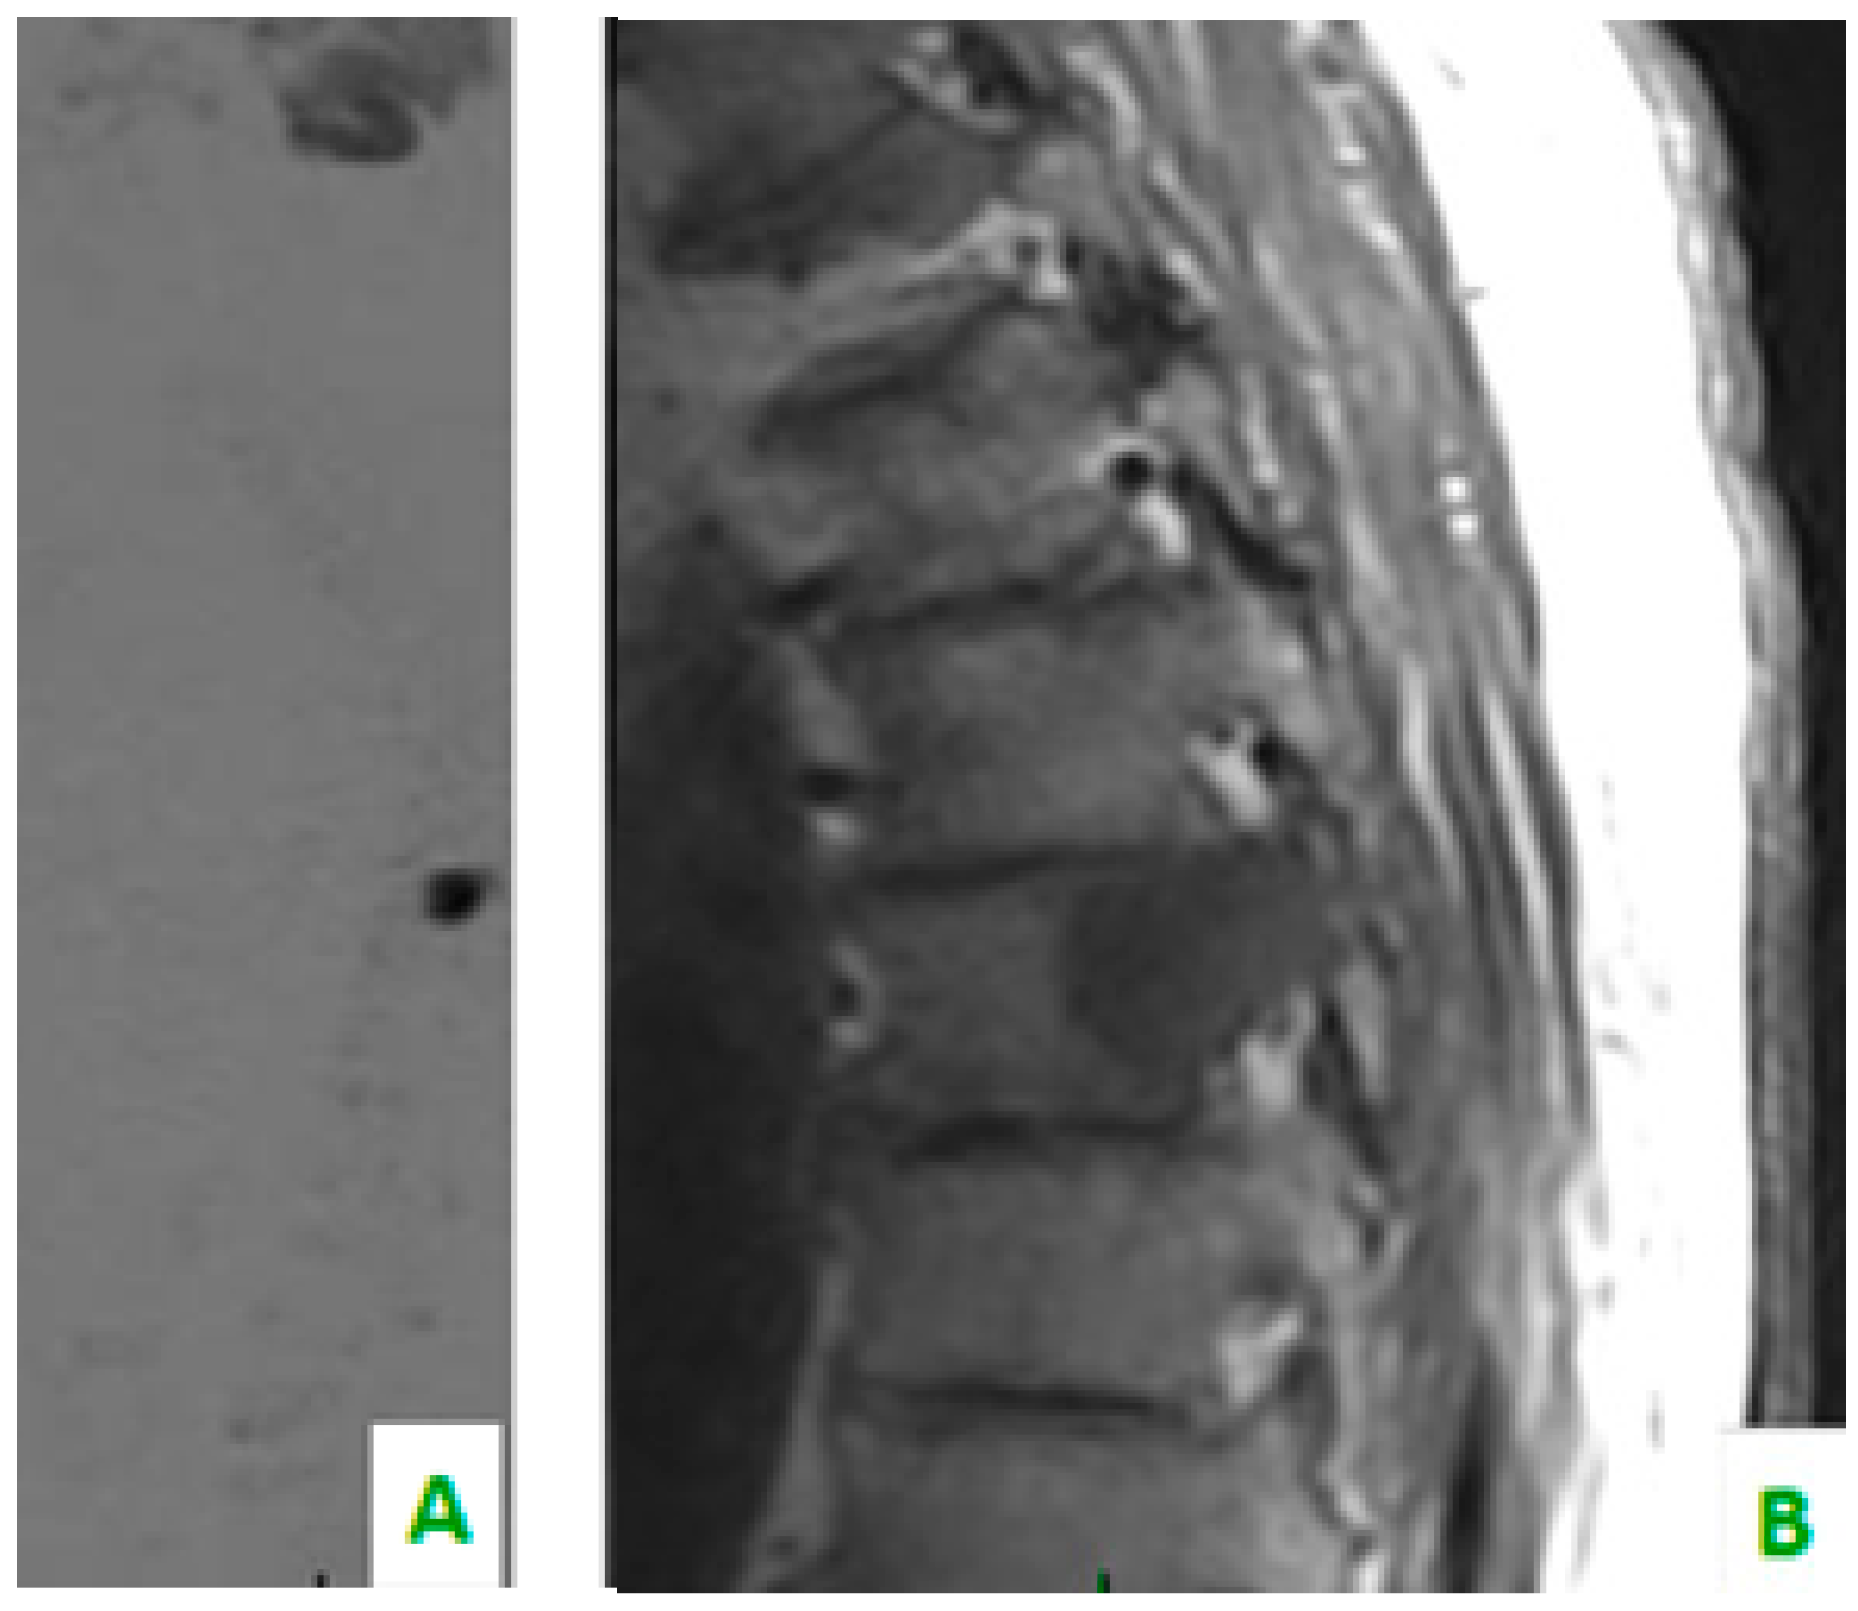

Figure 1. (A) Diffusion-weighted imaging (DWI) sequence in sagittal plane shows focal alteration of diffusivity. (B) The sagittal plane of TSE T1 shows, in the same level, a hypointense region of the dorsal soma related to the secondary localization of prostate cancer.

Despite the fact that there are numerous works that support the importance of WB-MRI-DWI for the identification of prostatic skeletal metastases in literature, this technique is not yet universally recognized, as evidenced in a recent work by Wieder et al. showing the superiority of 11C-choline PET/CT in detecting bone lesions (p = 0.02). In this work, however, no difference was reported in the detection of lymph node metastasis (p = 0.65) [20] (Figure 1).